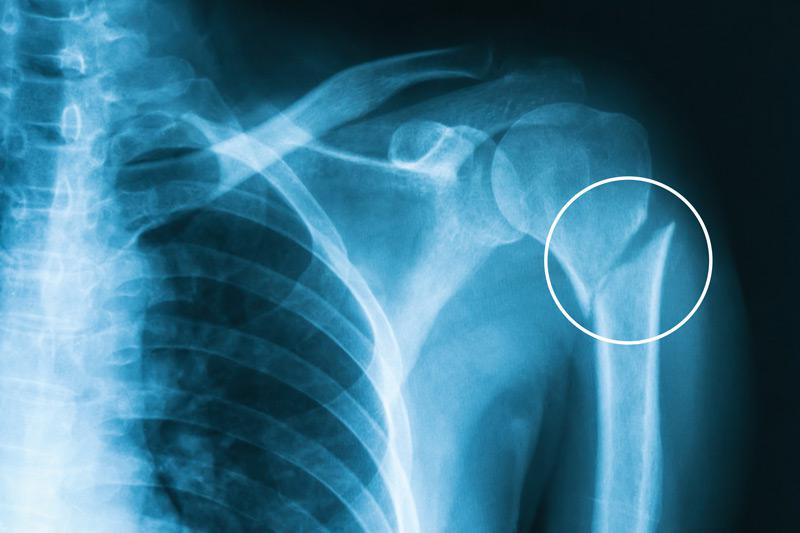

Supracondylar humerus fractures

If you break your humerus right above your elbow, you might have what’s called a supracondylar fracture. This is a type of elbow fracture that almost always affects kids. Supracondylar humerus fractures are usually caused by a child catching themselves from a fall with their arm stretched out in front of them. Your provider will diagnose and treat a supracondylar fracture like any other broken bone.

- X-rays: An X-ray will confirm any fractures, and show how damaged your bones are.